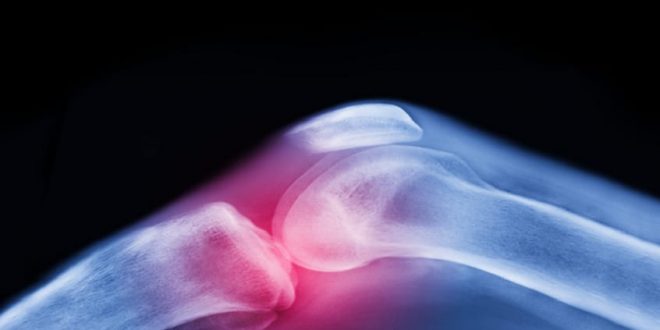

تعتبر آلام المفاصل وتيبّس الركبتين وأوجاع الوركين من الشكاوى الشائعة بين كبار السن، وغالبا ما يُقبل بها كجزء طبيعي من أعراض الشيخوخة.

لكن الواقع الطبي يوضح أن هذا ليس مصيرا حتميا، فالفصال العظمي — أكثر أمراض المفاصل شيوعا في العالم — يمكن الوقاية منه وعلاجه بطرق غير دوائية فعّالة للغاية.

ولا يعتبر الفصال العظمي مجرد تآكل ميكانيكي للمفصل، بل مرضاً يؤثر على جميع مكوناته: السائل الزلالي والغضروف والعظم والأربطة والعضلات المحيطة، وحتى الأعصاب التي تدعم الحركة. وتستهدف الحركة المنتظمة جميع هذه العناصر، وتحافظ على صحة المفصل بكفاءة.

ويفتقر الغضروف، وهو طبقة واقية تغطي أطراف العظام، إلى إمدادات الدم المباشرة ويعتمد على الحركة للبقاء صحيا. فهو يعمل مثل الإسفنجة: ينضغط عند الحركة، فيخرج السوائل ويعيد امتصاص المغذيات، ما يحافظ على مرونة المفصل وصحته.